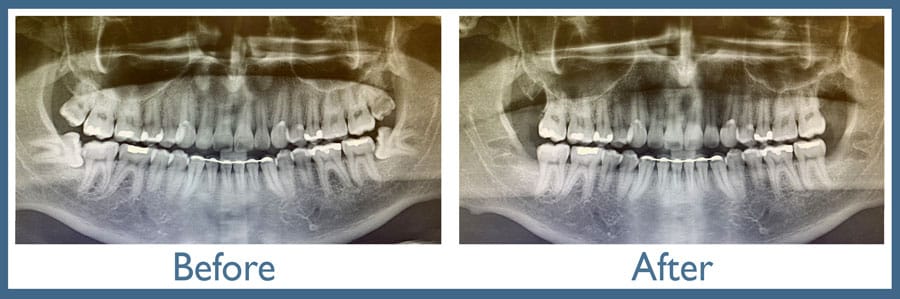

Latest imaging technology: